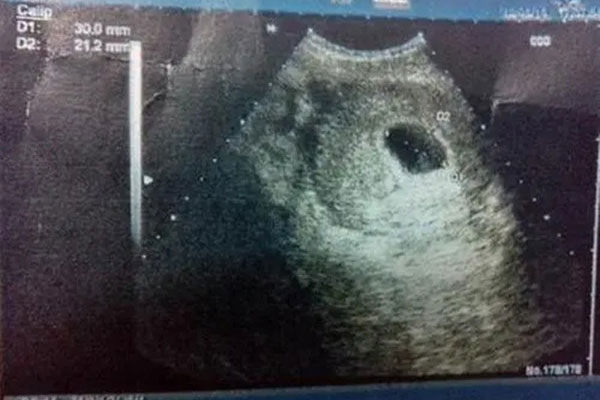

网传:孕囊长条状的是怀男孩;怀孕椭圆状的是怀女孩。可是,长孕囊和圆孕囊的区别在哪里呢?赶快一起来听听过来人的经验之谈吧!

一般说来,如果孕囊的形状像茄子,或者是呈长条状的,则怀上男宝宝;如果孕囊是椭圆形或圆形的,那么很可能就是个女宝宝了。

怀孕40天的B超,上面有说孕囊的数据,我看了一下三个数据,有两个差不多,其中有一个成倍成长,看样子是长条状的,后来生了儿子。

孕囊长条或圆形的,非常容易识别的。长条的孕囊,数据是成倍增长的,而且B超图像是也是可以看出来的哦。

孕囊大小的长和宽相差一倍以上,那么男宝宝可能性大。长和宽相等,或者相差不大的话,很可能是个女宝宝。

我怀孕8周时,孕囊大小是16mm17mm,结果生下了一位小公主。

怀孕两个多月时,孕囊大小是12mm 42mm 12mm,结果生的儿子。